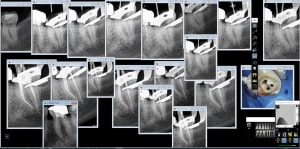

Radio_capteur_trophy_csvf5t.jpg

zoom_1570258573_suxrtb.jpg

zoom_1570258527_nvj0tg.jpg

zoom_1570258095_wh88wn.jpg